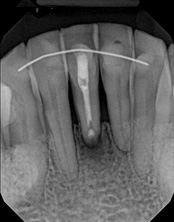

The patient was told by a specialist that the root canal failed, the only option was extraction and an implant. She did not want to do that; she wanted to keep her tooth, after all, it is her front tooth. She found us. We performed an apical microsurgery with the laser. The tooth was saved and is still functioning. This is a poor area for an implant, so much better to save the tooth.